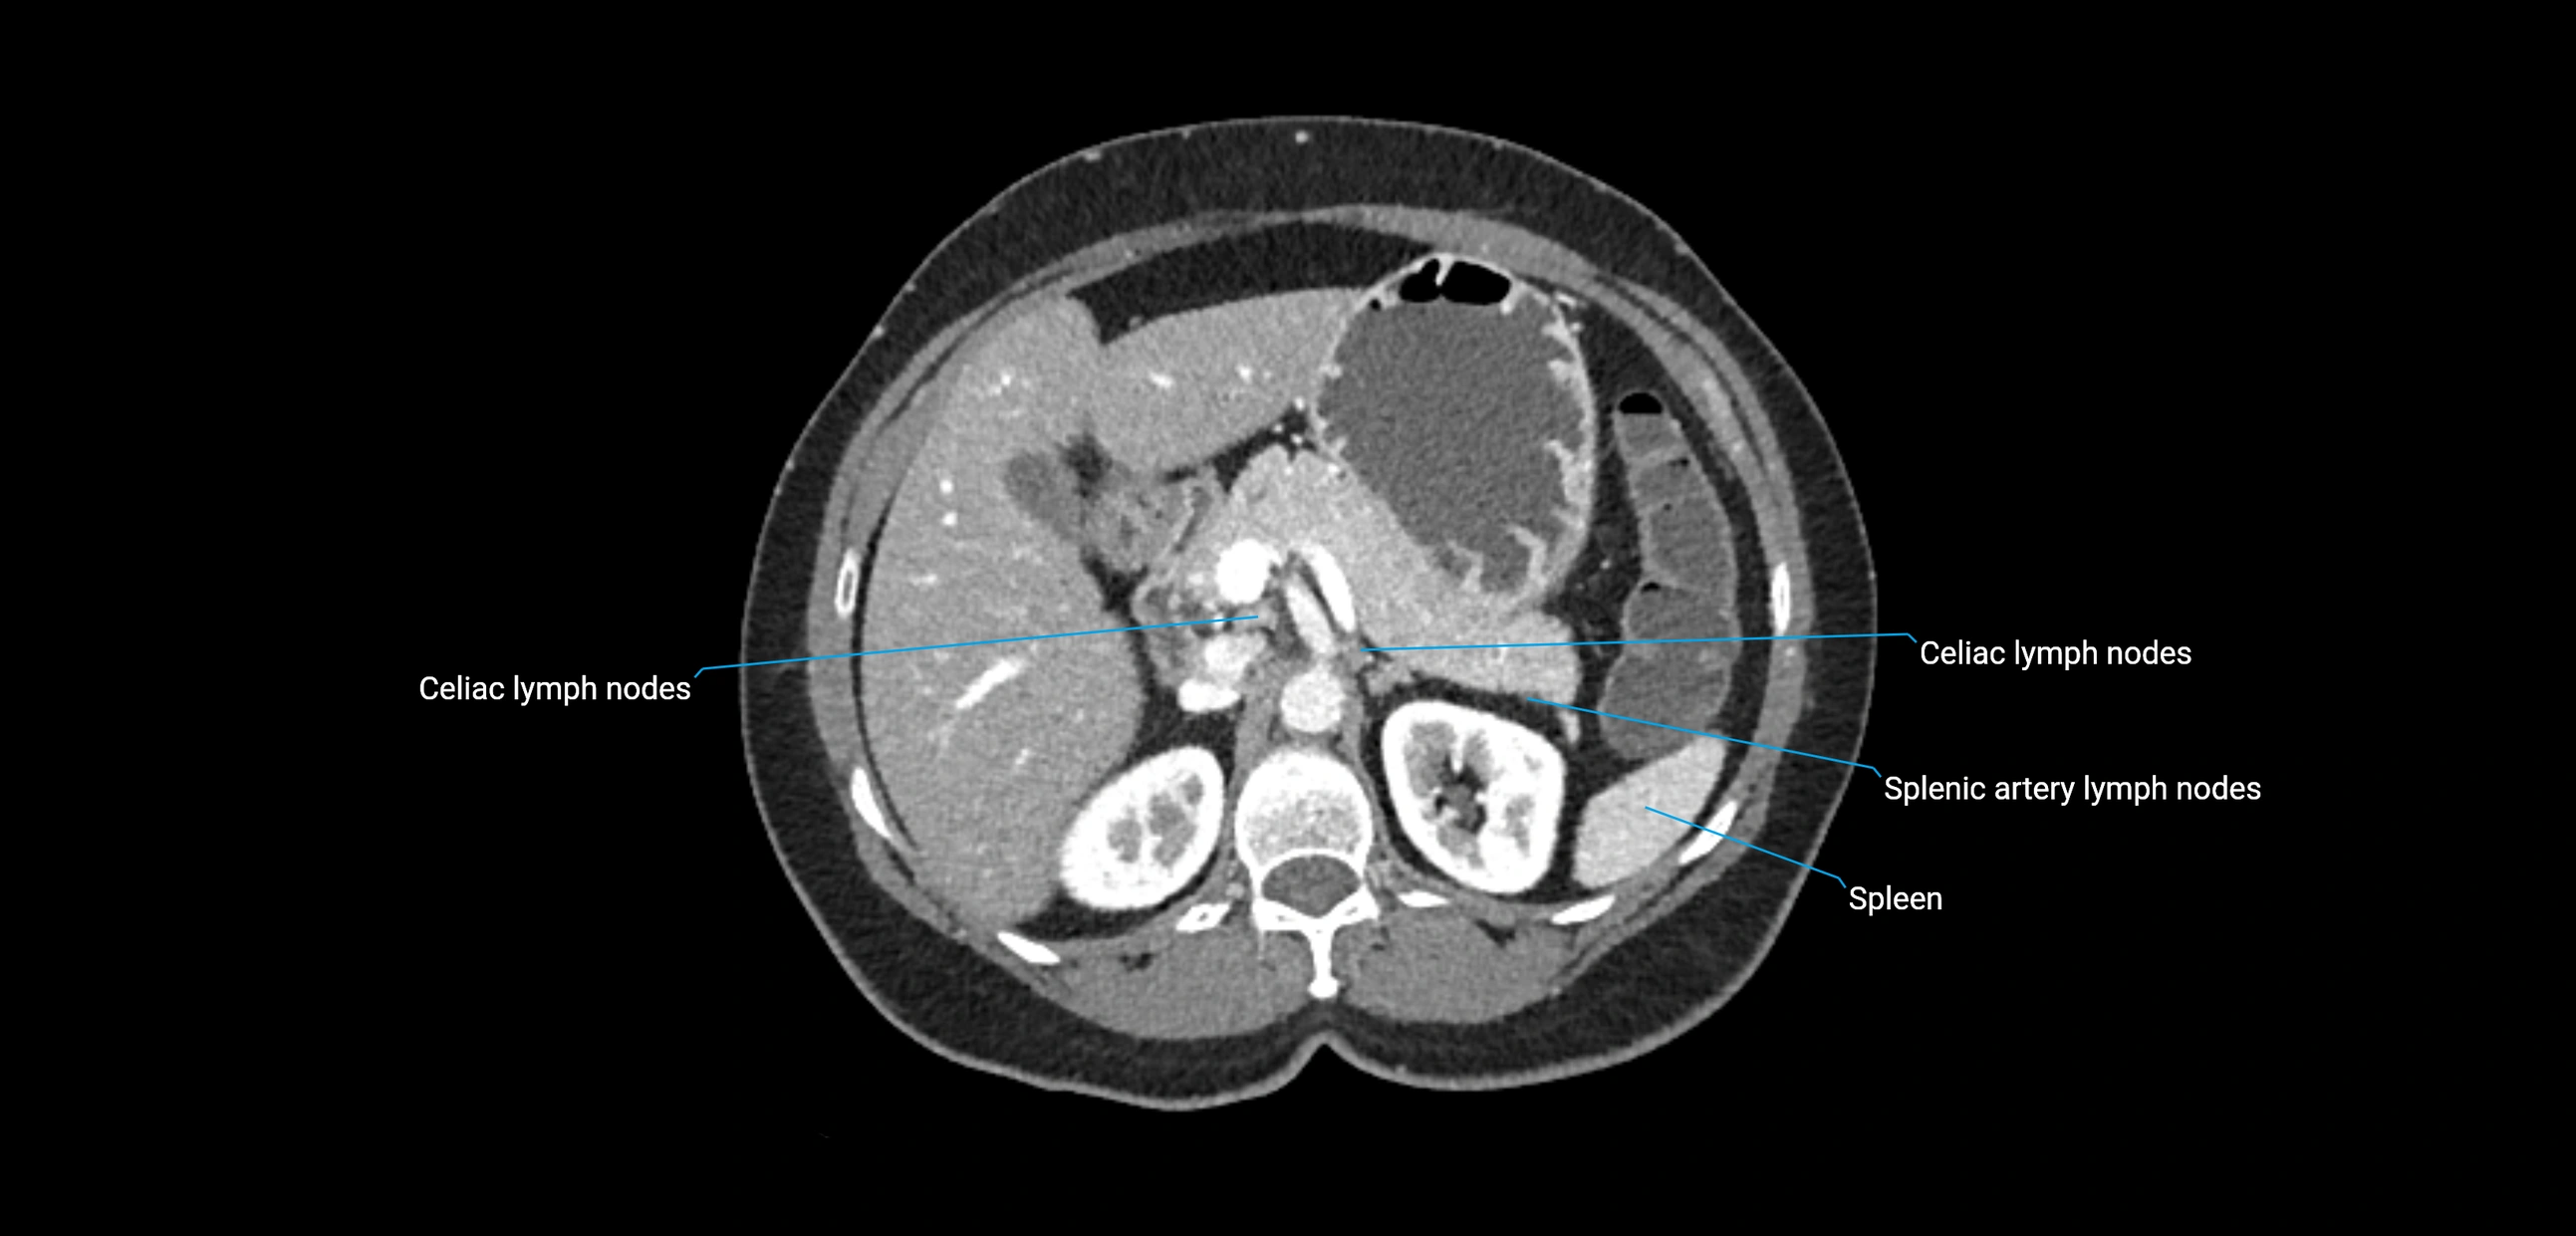

The lateral aortic lymph nodes (also called para-aortic lymph nodes) are a major group of retroperitoneal lymph nodes located along the abdominal aorta and its branches. They lie between the diaphragmatic crura superiorly and the bifurcation of the aorta at L4 inferiorly.

They are positioned on both sides of the abdominal aorta:

• Right lateral aortic nodes: adjacent to the inferior vena cava (IVC)

• Left lateral aortic nodes: lateral to the abdominal aorta

These nodes receive lymph from a wide range of abdominal and pelvic structures. Specifically, they drain lymph from the kidneys, suprarenal glands, gonads (testes/ovaries), uterus, uterine tubes, and pelvic organs, before converging into the lumbar lymphatic trunks, which terminate in the cisterna chyli → thoracic duct.

CT Appearance

CT Post-Contrast:

• Normal nodes enhance homogeneously

• Malignant nodes may show heterogeneous enhancement, central necrosis, or conglomerate formation

• Size >1 cm short axis is suspicious, though morphology and distribution are equally important